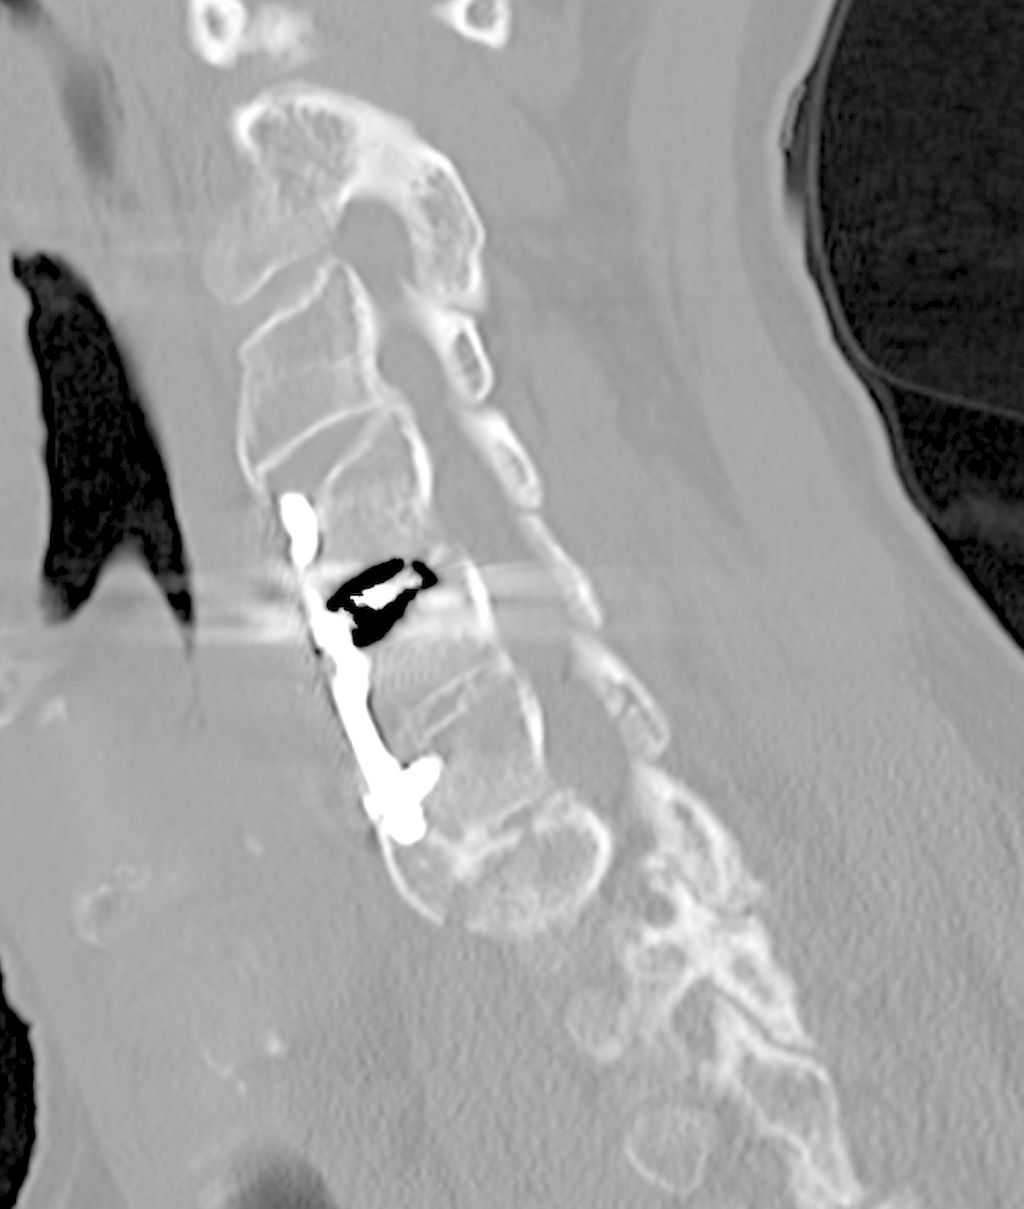

Fallbeispiel 1

Beispiel für die Implantation zervikaler Pedikelschrauben. In diesem Fall kam es bei einem 61-jährigen Patienten 10 Jahre nach anteriorer zervikaler Diskektomie und Fusion (ACDF) C4/5 und ventraler Verplattung C4–6 zu einer Ankylosierung auch von C6/7. Nach Sturz kam es zu einer Fraktur bei C6/7 mit begleitender Bogenfraktur und auch Beteiligung der dorsalen Ligamenta (Abb. 1 und 2). Klinisch bestanden ausgeprägte Nackenschmerzen und kein neurologisches Defizit. Es wurde die Indikation der dorsalen Verschraubung von C4 auf Th1 gestellt. Intraoperativ wurde routinemäßig zusätzlich eine kleine Referenzschraube in einer Lamina – entfernt von der Dornfortsatz-Referenzklemme für die Navigation – gesetzt. Mit dieser konnte intraoperativ die Genauigkeit der Navigation exakt überprüft werden (Abb. 4 und 5). Mittels navigierter High-Speed-Fräse wurden die Schraubenkanäle vorgebohrt (Abb. 6), im Anschluss wurde der Bohrkanal ausgetastet und die Schrauben wurden implantiert. Abbildung 7 zeigt eine Röntgenkontrolle 3 Monate postoperativ.